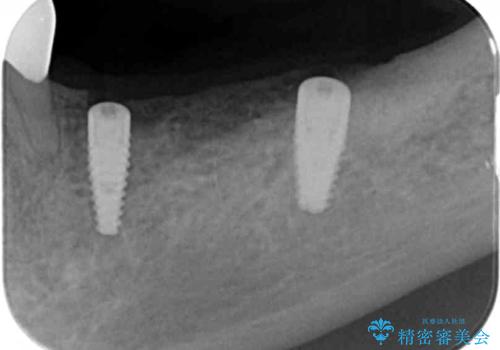

- 88万円 (インプラント・アバットメント・クラウン代全て含んで)費用は治療当時の料金となります

骨の量が比較的十分に保たれていたため、インプラントを埋入し1ヶ月後には仮歯を入れてしっかりと咬合機能を回復することができました。